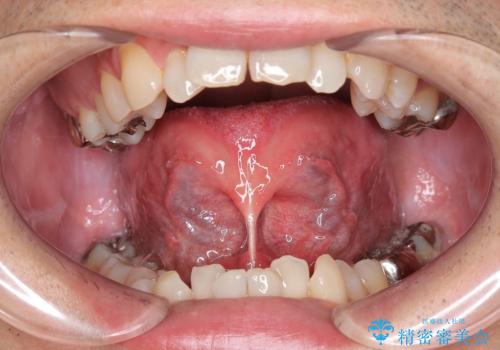

前歯の隙間とへこみが舌で触ると気になる|矯正治療は絶対にしたくない|抜歯即時インプラント+オールセラミッククラウンで審美修復